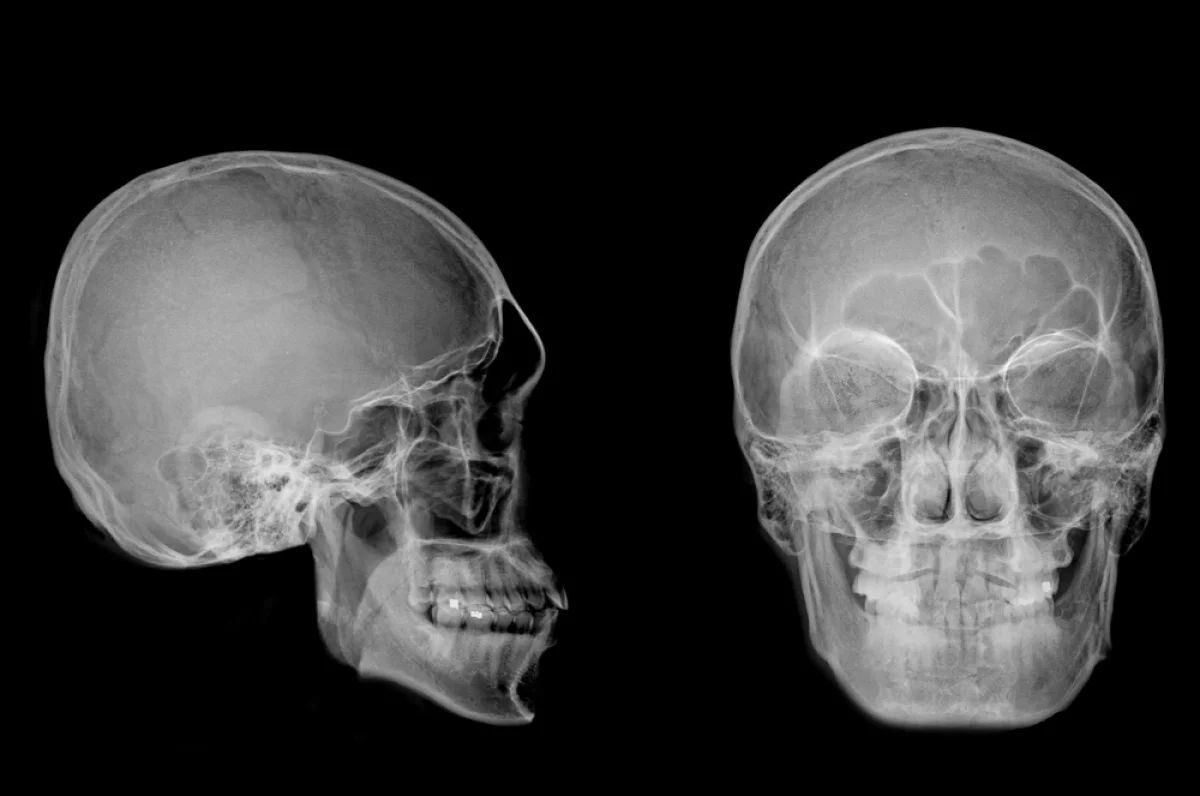

Краниопластика широко востребована не только у детей, но и среди совершеннолетних пациентов.

Краниопластика широко востребована не только у детей, но и среди совершеннолетних пациентов. istockphoto.com

Череп человека – это уникальная, сложная и прочная конструкция, которая защищает наш самый важный орган – головной мозг. Костные пластины, соединённые между собой эластичными швами, образуют не просто «броню», а динамичную систему, которая растёт сама, и обеспечивает нормальный рост и развитие головного мозга. Однако иногда в этой совершенной системе случаются сбои. тогда помочь пациенту может только челюстно-лицевой хирург.

Краниопластика широко востребована не только у детей, но и среди совершеннолетних пациентов. Краниопластику взрослых можно разделить на две группы: